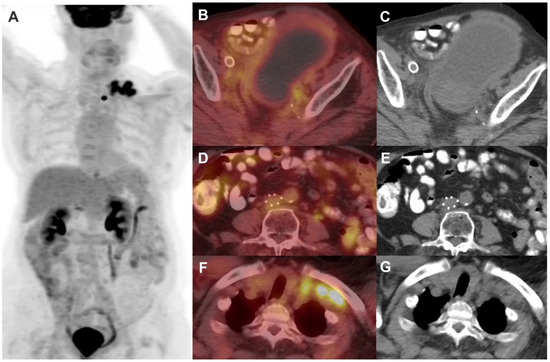

2. FDG PET/CT in Cervical Cancer

2.1. FDG PET in Staging

- Gandy, N.; Arshad, M.A.; Park, W.-H.E.; Rockall, A.G.; Barwick, T.D. FDG-PET Imaging in Cervical Cancer. Semin. Nucl. Med. 2019, 49, 461–470. [Google Scholar] [CrossRef]

- Pandit-Taskar, N.; Mahajan, S.; Ma, W. Diagnostic Applications of Nuclear Medicine: Uterine Cancers. In Nuclear Oncology: From Pathophysiology to Clinical Applications; Volterrani, D., Erba, P.A., Strauss, H.W., Mariani, G., Larson, S.M., Eds.; Springer International Publishing: Cham, Switzerland, 2020; pp. 1–45. ISBN 978-3-319-26067-9. [Google Scholar]